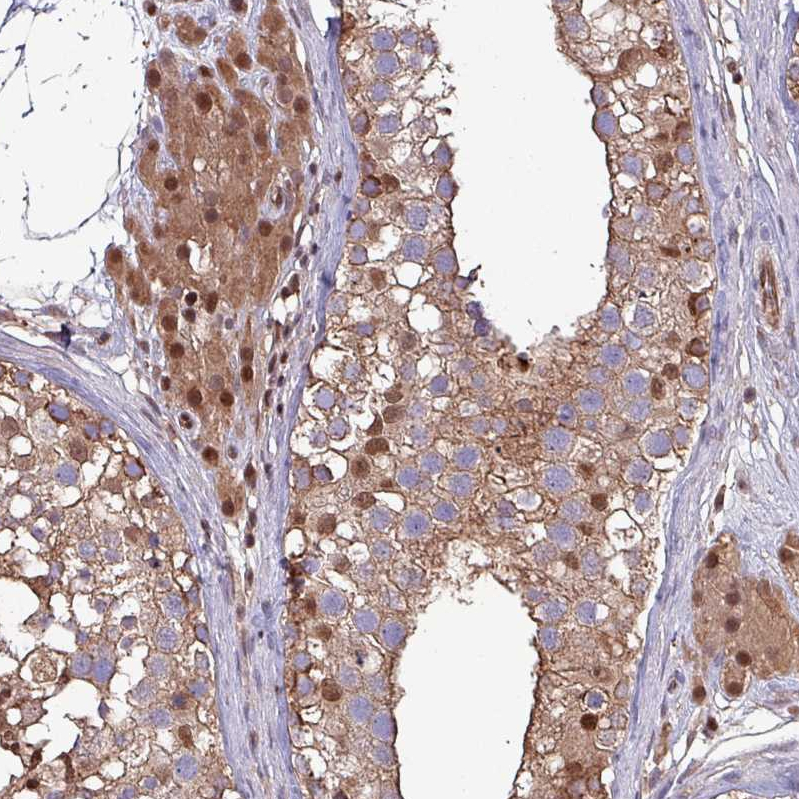

Immunohistochemistry analysis in human rectum and skeletal muscle tissues using HPA046995 antibody. Corresponding PSMB8 RNA-seq data are presented for the same tissues.